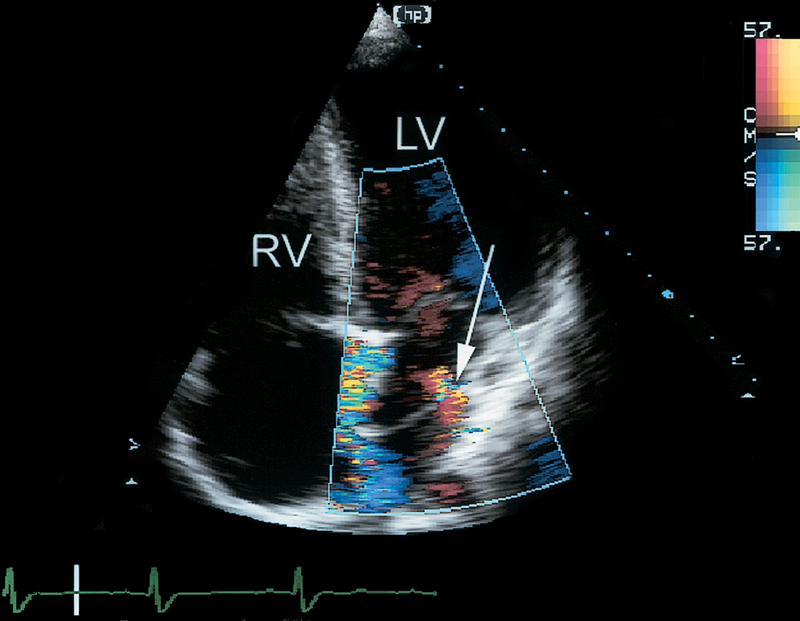

فحوصات تشخيصية لبعض امراض القلب والشرايين التاجية